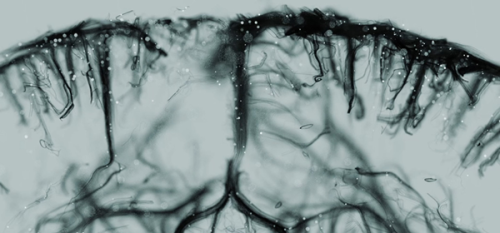

Les organes sont alimentés par un réseau complexe de vaisseaux sanguins, essentiels à leur bon fonctionnement. Certaines techniques d’imagerie donnent un aperçu global de ce réseau vasculaire, mais pour la première fois une imagerie 3D ultrarapide permet d’observer les flux sanguin des grosses artères jusqu’aux plus petits vaisseaux sanguins de seulement quelques micromètres de diamètre.

Depuis plusieurs années, le laboratoire Physique pour la Médecine Paris est un des leaders mondiaux en matière d’imagerie par ultrasons, non invasive et non ionisante. Ce laboratoire a accompli des avancées majeures en imagerie vasculaire au cours des dix dernières années, avec la mise au point de l’imagerie Doppler ultrasensible (uDoppler) et l’imagerie fonctionnelle ultrasonore (fUS) puis la microscopie de localisation ultrasonore (ULM) en 2D. La technologie est licenciée à la société Iconeus (start-up issue des travaux du laboratoire) dans le domaine de l’imagerie cérébrale, où elle trouve déjà de nombreuses applications pour la recherche en neurosciences. Les chercheurs de Physique pour la Médecine Paris viennent tout juste de remporter une nouvelle victoire en déployant l’ULM en 3D : grâce à l’aspect tridimensionnel, les chercheurs ont obtenu des images super-résolues du cœur et du cerveau de rongeur, à l’échelle de l’organe entier.

Pour atteindre une telle prouesse à des résolutions aussi fines, les scientifiques injectent des microbulles de gaz biocompatibles, dont la position est suivie à haute cadence d’imagerie. Il est ainsi possible de remonter aux informations détaillées sur le débit sanguin, la taille des canaux, et donc reconstituer l’activité vasculaire complète de l’organe. Outre les connaissances fondamentales sur le fonctionnement des organes, cette technique pourrait également fournir de précieuses informations sur différentes pathologies cardiovasculaires, voire mesurer l’efficacité de différents traitements.